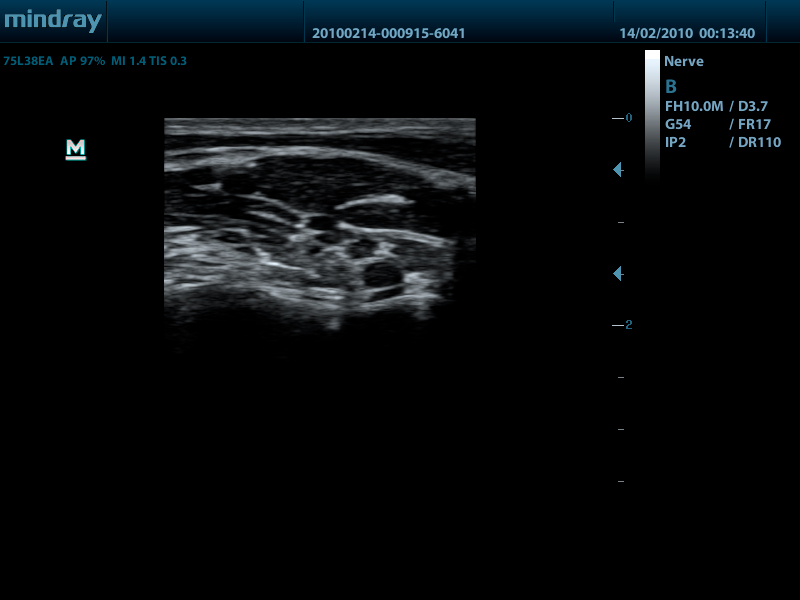

Mindray DP-50 – портативная цифровая ультразвуковая система с ЖК монитором 15 дюймов (1024Х768)

и встроенными аккумуляторными батареями (опция) позволяющими работать в автономном режиме до 2-х часов.

DP-50 – портативный УЗИ сканер разработан на базе новой платформы X-treme engine, используемой в хорошо зарекомендовавших себя цветных сканерах с доплером моделей DC-3, DC-7, DC-6. Эта платформа открывает возможности для расширений до уровня цветных сканеров и совместимости с широким диапазоном периферийного оборудования. X-treme означает интеллект, высокую скорость обработки данных, многоуровневую передачу сигналов, а также возможность оптимизации изображения и модульного расширения.

Применяемые датчики DP-50:

Линейный датчик 75L38EA (5.0/7.5/8.5/10.0/Н8.0/Н10.0 МГц, 38 мм)